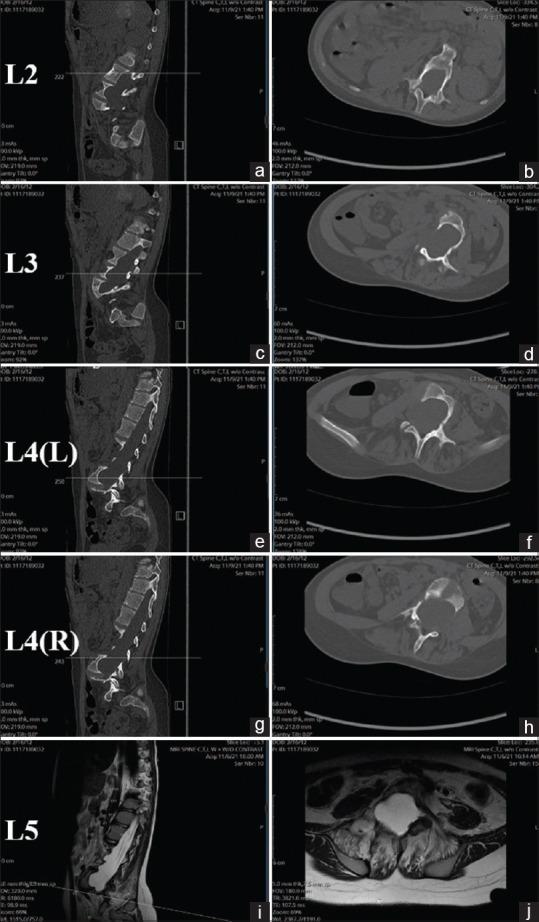

We report the use of computerized tomography (CT)-guided navigation for complex spinal deformity correction (anterior and posterior) in an 8-year-old patient with neurofibromatosis complicated by dystrophic pedicles, dural ectasia, and extensive vertebral scalloping. A retrospective review was conducted of the patient's medical records for the past 3 years, including the patient's office visit notes, operative reports, pre- and 2-year postoperative imaging studies. The patient successfully underwent anterior lumbar interbody fusion from L3-S1 using CT-guided navigation to negotiate the challenges posed by dural ectasia and vertebral body scalloping. One week after the anterior procedure, she underwent navigation-guided T10-to-pelvis posterior instrumented fusion. There were no perioperative or postoperative complications at 2 years. In patients with complex deformities of the spine, including dural ectasia, scalloped vertebral bodies, and decreased pedicle integrity, the use of intraoperative CT-guided navigation can benefit surgeons by facilitating the safe placement of interbody spacers and pedicle screws.

我们报告了在一名8岁神经纤维瘤病患者中使用计算机断层扫描(CT)引导导航进行复杂脊柱畸形矫正(前路和后路)的情况,该患者伴有营养不良性椎弓根、硬脊膜扩张和广泛的椎体扇贝样变。对该患者过去3年的病历进行了回顾性分析,包括患者的门诊记录、手术报告、术前和术后2年的影像学研究。患者成功接受了L3-S1前路腰椎椎间融合术,使用CT引导导航应对硬脊膜扩张和椎体扇贝样变带来的挑战。前路手术后一周,她接受了导航引导下的T10至骨盆后路器械融合术。2年时无围手术期或术后并发症。对于患有复杂脊柱畸形的患者,包括硬脊膜扩张、扇贝样椎体和椎弓根完整性降低,术中使用CT引导导航可通过促进椎间融合器和椎弓根螺钉的安全置入而使外科医生受益。